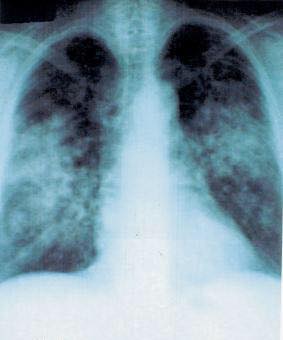

مراحل داء الساركويد.. وعادة ما يتم التشخيص داء الساركويد بأخذ التاريخ المرضي واجراء الفحص السريري وعمل أشعة الصدر التي قد تحدد نوعية المرض وشدته، ويعد فحص الأشعة المقطعيه من الفحوصات المهمة للمساعده في تشخيص الحالة ومقدار تأثر الرئة والغدد الليمفاوية.

ينقسم الساركويد إلى أربعة مراحل تبعا لمقدار تأثر الرئتين والغدد الليمفاوية نوردها كالتالي:

- المرحلة الأولى، وهى عبارة عن تورم في الغدد الليمفاوية الرئوية.

- المرحلة الثانية، وهى تورم في الغدد الليمفاوية الرئوية والتهاب تليفي في الرئتين.

- المرحلة الثالثة، وهي التهاب تليفي في الرئتين.

- المرحلة الرابعة وهي تليف في الرئتين.

الدلائل الأساسية للمرض والتي تظهر لدى تصوير الصدر هي اتساع بوابات الرئتين بواسطة العقيدات اللمفاوية، وكذلك حدوث إرتشاح طفيف في أنسجة الرئتين.

ويمكن الحصول على هذه الدلالات بصورة أدق وأفضل بمساعدة التصوير المقطعي للصدر.